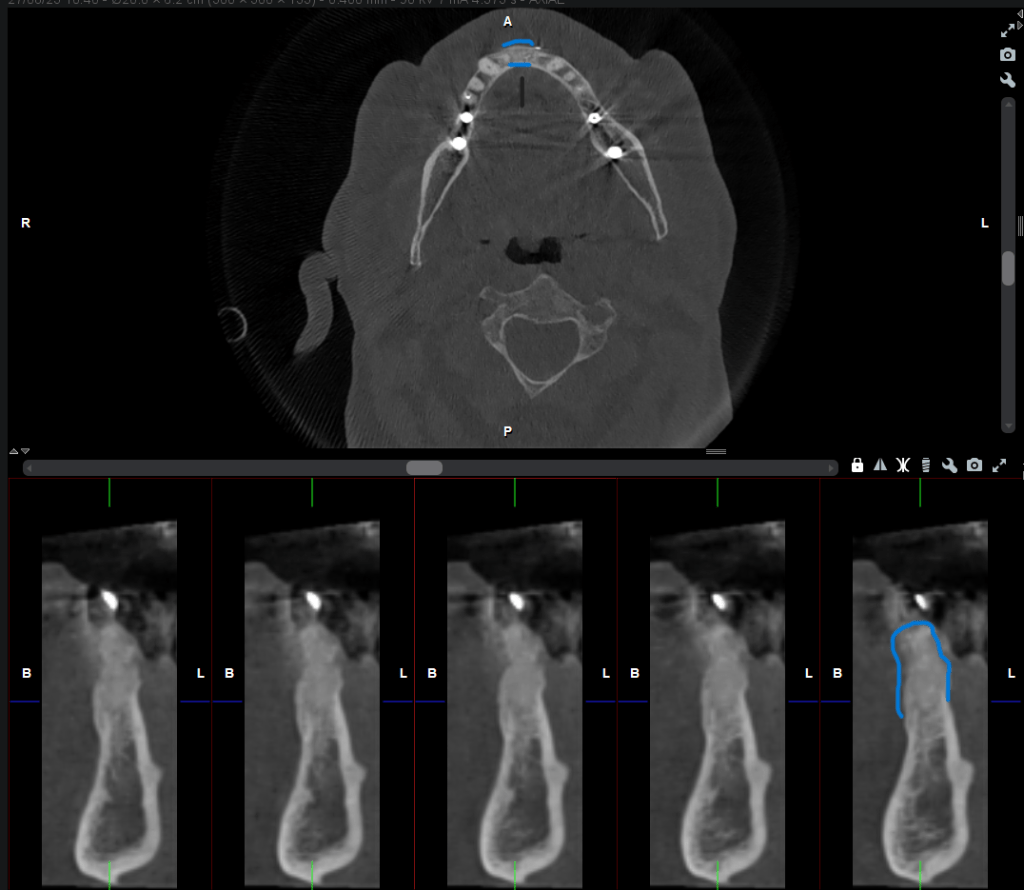

Tras realizar un diagnóstico por imagen en 3D, observamos la pérdida total de la cortical vestibular y lingual a nivel del 4.1 (Figura 7 -8).